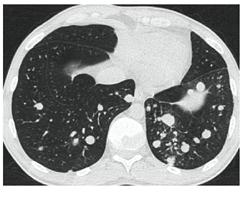

2. Наличие клинических проявлений, указанных в п. 1, в сочетании с характерными изменениями в легких по данным компьютерной томографии (КТ) (см. Приложение 1 настоящих рекомендаций) вне зависимости от результатов однократного лабораторного исследования на наличие РНК SARS-CoV-2 и эпидемиологического анамнеза.

- Изменения при КТ (рентгенографии), типичные для вирусного поражения (объем поражения минимальный или средний; КТ 1-2)

- Изменения в легких при КТ (рентгенографии), типичные для вирусного поражения (объем поражения значительный или субтотальный; КТ 3-4)

- Изменения в легких при КТ (рентгенографии), типичные для вирусного поражения критической степени (объем поражения значительный или субтотальный; КТ 4) или картина ОРДС.

КТ имеет высокую чувствительность в выявлении изменений в легких, характерных для COVID-19. Применение КТ целесообразно для первичной оценки состояния ОГК у пациентов с тяжелыми прогрессирующими формами заболевания, а также для дифференциальной диагностики выявленных изменений и оценки динамики процесса. КТ позволяет выявить характерные изменения в легких у пациентов с COVID-19 еще до появления положительных лабораторных тестов на инфекцию с помощью МАНК. В то же время, КТ выявляет изменения легких у значительного числа пациентов с бессимптомной и легкой формами заболевания, которым не требуется госпитализация. Результаты КТ в этих случаях не влияют на тактику лечения и прогноз заболевания при наличии лабораторного подтверждения COVID-19. Поэтому массовое применение КТ для скрининга асимптомных и легких форм болезни не рекомендуется.